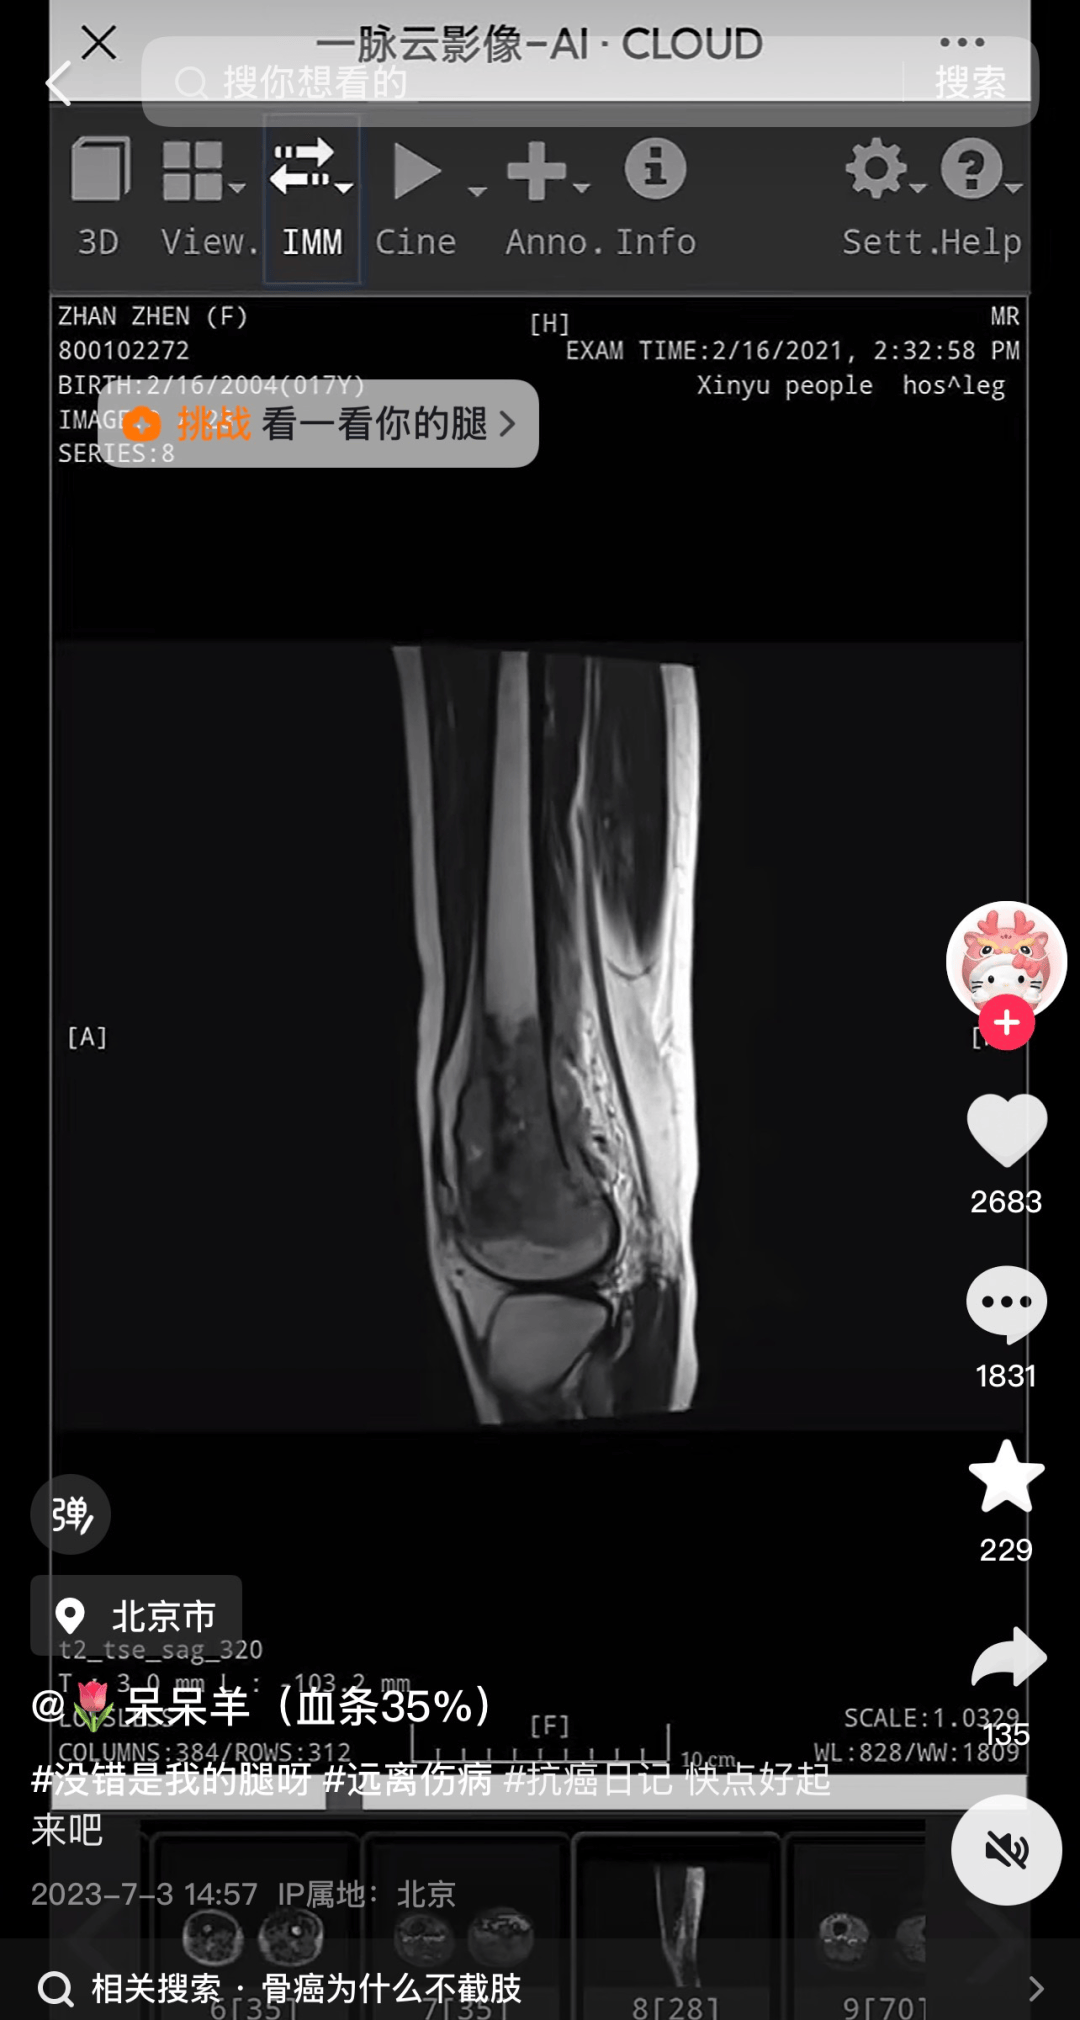

记者发现,网红“呆呆羊(血条35%)”抖音账号有16.7万粉丝,2023年7月3日,“呆呆羊”更新首条内容,视频中“呆呆羊”发布了自己的诊断报告,时间为2021年2月16日虚拟币trump币